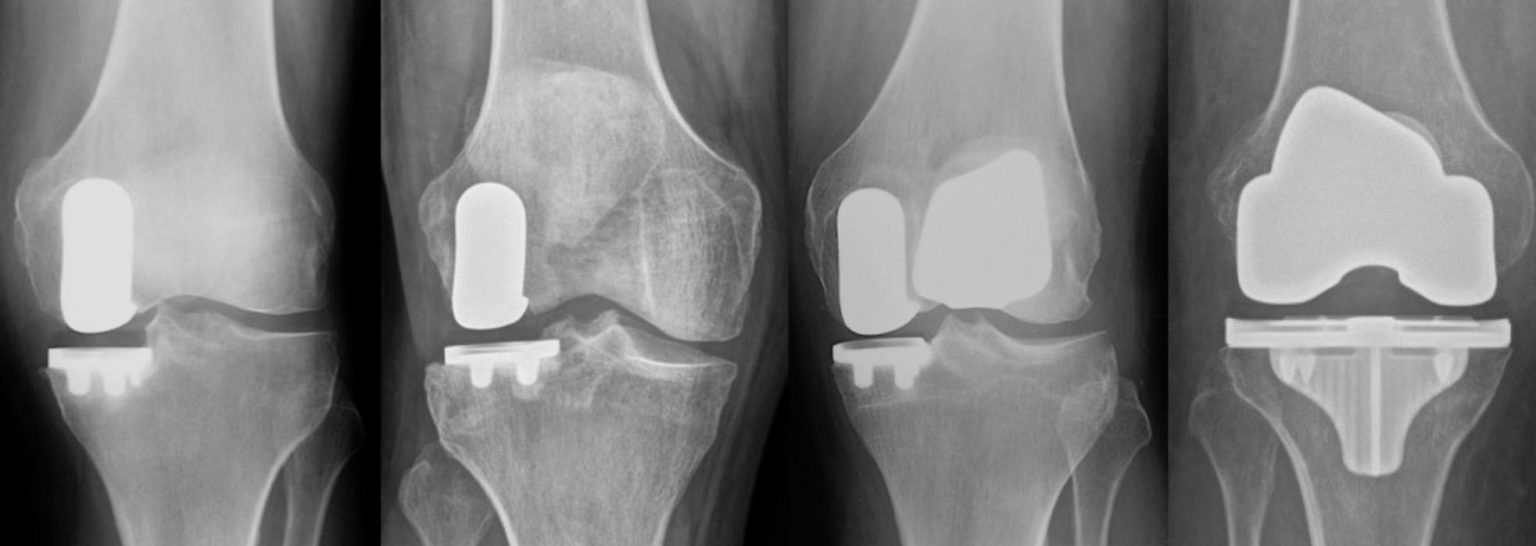

Is Robotic Total Knee Replacement Better . Web  robotic total knee arthroplasty (tka) has demonstrated improved component positioning and a reduction of. I use robotics when there’s.

I use robotics when there’s. Web  robotic total knee arthroplasty (tka) has demonstrated improved component positioning and a reduction of.